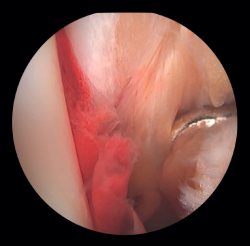

If possible, we reinsert unstable osteochondral fragments (Figure 3). In chondral lesions where it is not possible to reinsert the fragment, cartilage repair stimulation techniques can be used(5,13).

Figure 3. A: loose bodies; B: osteochondral lesion; C: reduction of the osteochondral lesion; D: medullary stimulation.